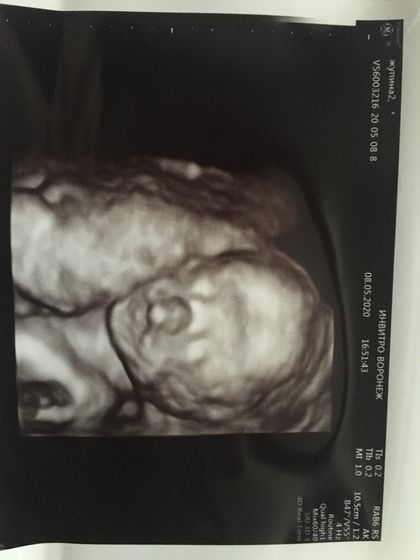

Привет всем). Живот уже очень заметен. Пупочек не вылез, но чувствую вот вот и он выпрыгнет) малыш постоянно выдавливает на пупок. Шевеления чувствую хорошо. Последние 2 дня ребёночек вообще не угомонный) танцует по всему животу) раньше чувствовала шевеления в основном когда лежала или сидела, а сейчас стою или иду, без разницы, чувствую и вижу как он там бьется) иногда вылазит в одно место и получается вот такой ширик, по ощущением это головкой он вылез) в основном по утрам так вылазит) вот мой животик) с первого скрининга нам говорят что мальчик) фото малыша на 19 неделе второе фото, на 21 неделе первое фото. Молозиво течёт сильно, ношу подкладки под грудь. Ходила на узи из-за непонятных схваток. Но уже поняла что это тренировочные. Знаю что тренировочные, так как врач сказал, не сама придумала)первая беременность, по этому не знаю ничего, и из-за этого постоянно переживаю. Вес у нас на 21 неделе 405 грамм) по показателям все в норме) делитесь своими ощущениями, фотографиями)